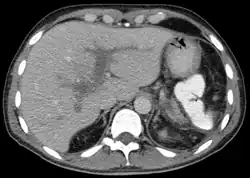

| Portal vein thrombosis seen with computed tomography. | |

The diagnosis of portal vein thrombosis is usually made with imaging confirming a clot in the portal vein; ultrasound is the least invasive method and the addition of the Doppler technique shows a filling defect in blood flow. PVT may be classified as either occlusive or nonocclusive based on evidence of blood flow around the clot.[5] An alternative characterization based on site can be made: Type 1 is limited to the main portal vein, Type 2 involves only a portal vein branch (2a, or 2b if both branches are affected), and Type 3 if clot is found throughout both areas.[8] Determination of condition severity may be derived via computed tomography (CT) with contrast, magnetic resonance imaging (MRI), or MR angiography (MRA). Those with chronic PVT may undergo upper endoscopy (esophagogastroduodenoscopy, EGD) to evaluate the presence of concurrent dilated veins (varices) in the stomach or esophagus.[3] Other than perhaps slightly elevated transaminases, laboratory tests to evaluate liver function are typically normal.[1] D-dimer levels in the blood may be elevated as a result of fibrin breakdown.